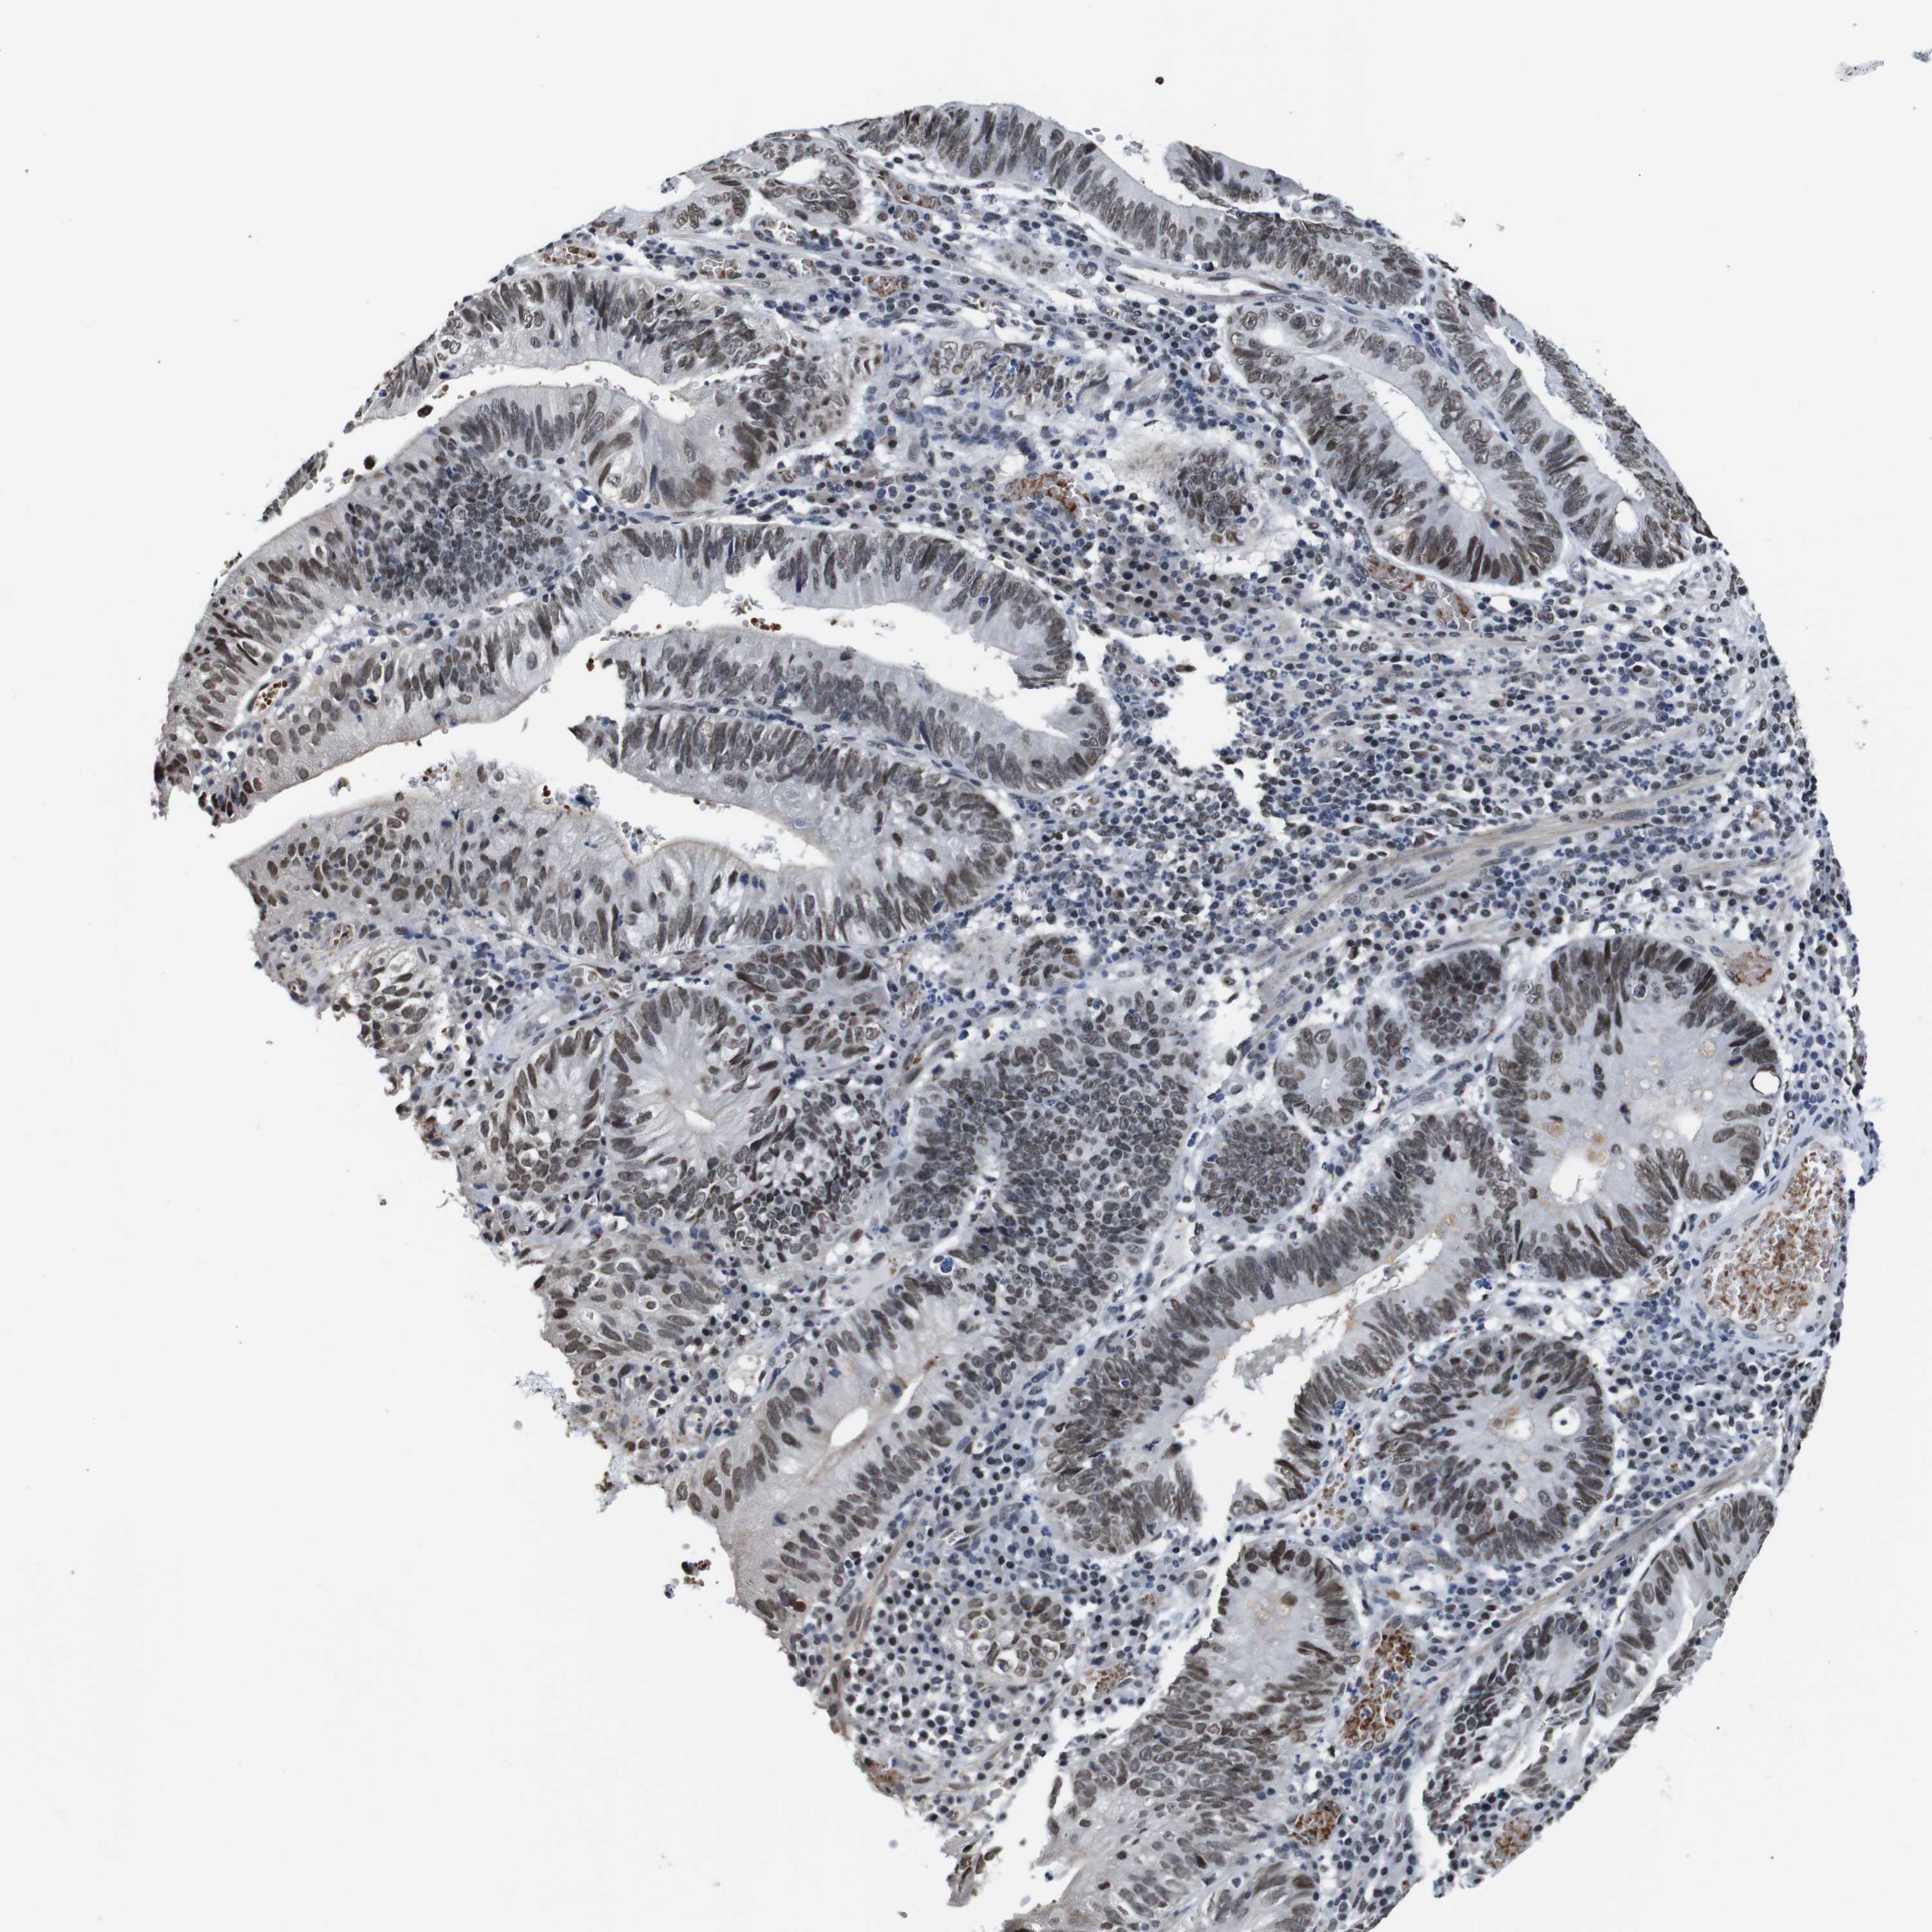

STOMACH CANCER - Protein expressioni

A mouse-over function shows sample information and annotation data. Click on an image to view it in a full screen mode. Samples can be filtered based on level of antibody staining by selecting one or several of the following categories: high, medium, low and not detected. The assay and annotation is described here.

Note that samples used for immunohistochemistry by the Human Protein Atlas do not correspond to samples in the TCGA dataset.

Antibody stainingi

Antibody staining in the annotated cell types in the current human tissue is reported as not detected, low, medium, or high, based on conventional immunohistochemistry profiling in selected tissues. This score is based on the combination of the staining intensity and fraction of stained cells.

Each image is clickable and will lead to virtual microscopy that enables deeper exploration of all samples and also displays staining intensity scores, fraction scores and subcellular localization as well as patient and tissue information for each sample.

Antibody HPA012545

Staining

High

Medium

Low

Not detected

Intensity

Strong

Moderate

Weak

Negative

Quantity

>75%

75%-25%

<25%

None

Location

Nuclear

Cytoplasmic/membranous

Cytoplasmic/membranous,nuclear

Adenocarcinoma, NOS

Adenocarcinoma, High grade